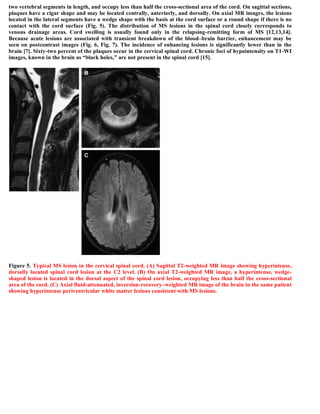

This document discusses a case of spinal multiple sclerosis in a 40-year-old patient. MRI images show well-defined pencil-shaped lesions occupying 2-3 spinal segments that are hypointense on T1-weighted images and hyperintense on T2-weighted images. Diffuse abnormalities are also seen as poorly demarcated hyperintense regions on T2-weighted images. The diagnosis is spinal multiple sclerosis. The document then discusses features of spinal MS lesions seen on MRI such as focal lesions, diffuse abnormalities, and spinal cord atrophy, and compares features of MS to other conditions like neuromyelitis optica.